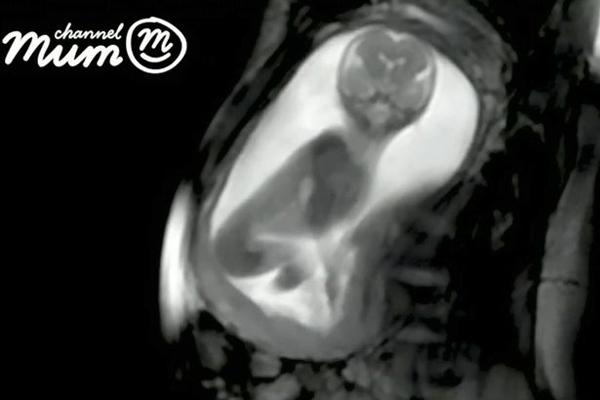

Những hình ảnh rõ nét sẽ giúp phát hiện các dị tật bẩm sinh.

Chia sẻ thêm về công nghệ siêu âm mới này, tiến sĩ David Lloyd cho biết: "Siêu âm thai nhi 20 tuần không phải công việc dễ dàng bởi vì bé còn rất nhỏ. Ví dụ như trái tim của thai nhi, bao gồm cả các ngăn và van cũng chỉ dài khoảng 15mm, nhỏ hơn 1 đồng xu. Siêu âm thông thường khó có thể phát hiện vấn đề ở những bộ phận nhỏ như vậy.

Quan trọng hơn là công nghệ siêu âm mới chúng tôi đang nghiên cứu hoàn toàn an toàn khi sử dụng trong thai kỳ".

Công nghệ siêu âm mới hoàn toàn an toàn cho thai nhi.